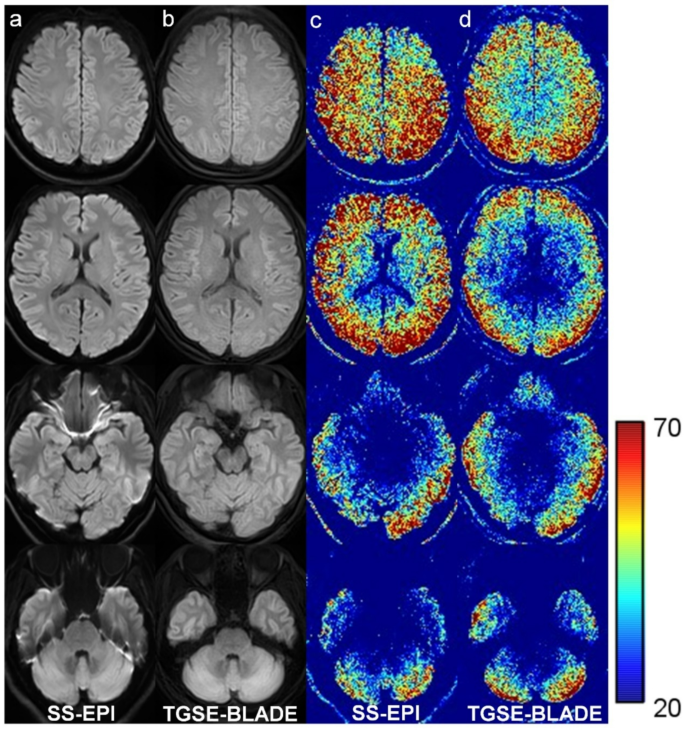

Mean SNR in CSO was significantly higher in SS-EPI DWI (26.3 ± 7.0) than TGSE-BLADE DWI (22.0 ± 5.5) (p < .001), but showed no significant difference in pons (SS-EPI DWI, 9.7 ± 3.0; TGSE-BLADE DWI, 9.5 ± 1.8) (p = .40). Mean SNR values were higher at the periphery and lower at the center of the brain in the SNR maps for both DWI sequences due to the characteristics of the 32-channel phased array coil (Fig. 4). Mean SNR in CSO was higher in SS-EPI DWI than TGSE-BLADE DWI; however, SNR in temporal lobe was higher in TGSE-BLADE DWI, probably because this sequence is less prone to susceptibility artifacts. Mean CNR was significantly higher in SS-EPI DWI (20.5 ± 12.1) than TGSE-BLADE DWI (15.5 ± 11.1) (p < .001).

Representative b1000 images (a, b) and SNR maps (c, d) of SS-EPI DWI (a, c) and TGSE-BLADE DWI (b, d) are shown in a healthy volunteer.